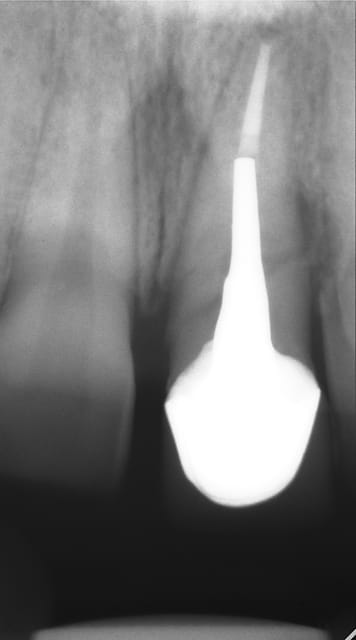

J'ai de tout en boutique..jeune homme 25 ans accident de piscine choc sur la bordure ( fêlure existante..fistule), extraction le jour même, temporisation 4 mois (avec un bout de trombone) Monobloc 16mm 60N, prep cap zircone droit 2/2 provisoire ion, temporisation 3 mois ceramo ceram..

J'ai de tout en boutique..jeune homme 25 ans accident de piscine choc sur la bordure ( fêlure existante..fistule), extraction le jour même, temporisation 4 mois (avec un bout de trombone) Monobloc 16mm 60N, prep cap zircone droit 2/2 provisoire ion, temporisation 3 mois ceramo ceram.. suite des photos :)